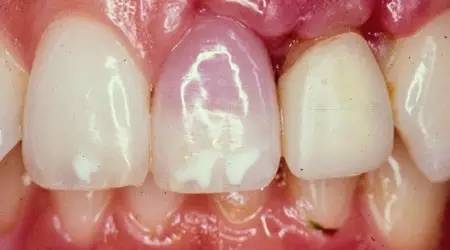

8、牙齿变暗、发黑

牙齿外伤后颜色改变可能有两点原因:要么是为了保护神经,要么是已经死了。

如果是保护神经,牙齿可能比邻牙看起来暗一点。如果像挫伤一样改变颜色(从粉红到灰白),意味着牙齿很有可能死亡,可能需要根管治疗后冠修复治疗。在某些情况下,可能需要拔除牙齿。如果是乳牙,可以不用管,直到脱落。